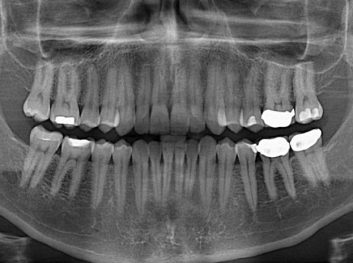

損壞的牙齒如何自我修復(fù)?近日,來自哈佛大學(xué)和諾丁漢大學(xué)的研究人員研發(fā)了能夠刺激牙齒干細(xì)胞再生的新型生物材料,而這種新材料研發(fā)成功的背后,正源于他們對牙齒如何實(shí)現(xiàn)自我修復(fù)這個(gè)課題的不斷探索。

據(jù)美國期刊《大眾科學(xué)(Popular Science)》報(bào)道,此種新型生物材料,不僅可以有效地取代傳統(tǒng)補(bǔ)牙填充物,刺激牙齒干細(xì)胞再生,患者也有望無需再接受根管治療,使蛀牙患者免除牙根感染或牙髓壞死的苦惱,一個(gè)全新的牙齒治療時(shí)代即將來臨。

Adam Celiz,是來自諾丁漢大學(xué)的研究人員,他和同事開發(fā)的這種新型合成生物材料,能刺激干細(xì)胞在牙髓部的生長。與普通材料一樣,這種合成材料被填充到牙齒并用UV光硬化。

在體外測試中,材料刺激干細(xì)胞進(jìn)入牙本質(zhì)的增殖和分化速度,促進(jìn)形成牙齒骨組織。研究人員認(rèn)為,一旦材料在受損牙齒中應(yīng)用,這些干細(xì)胞可以自動修復(fù)來自填充物上的損壞。在本質(zhì)上,該生物材料將使牙齒自愈。